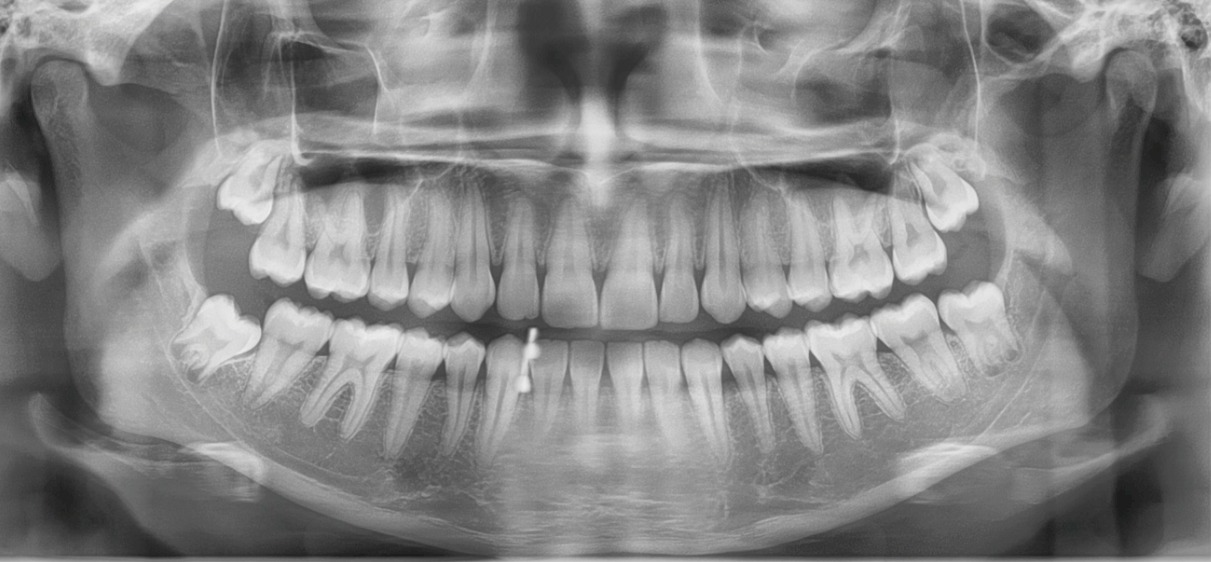

Dente deitado

Dente inclinado